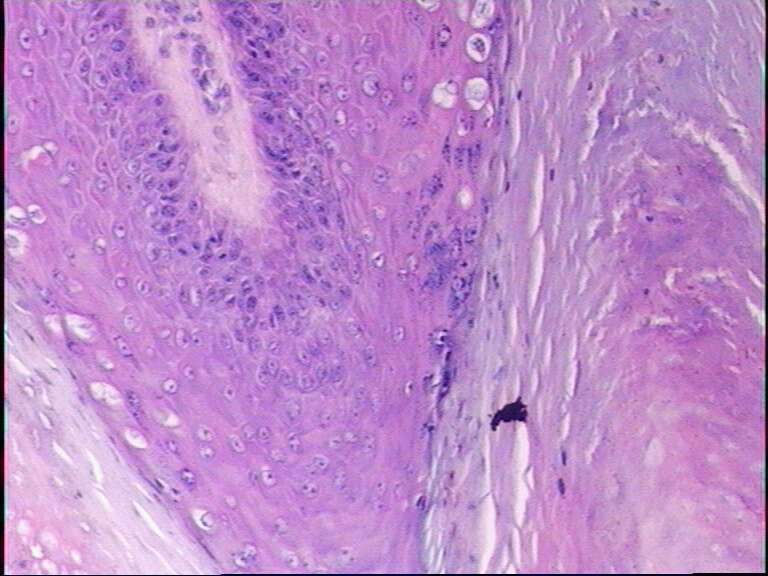

男38岁,手指肿物一年

寻常疣

最后一张典型的寻常疣构型

寻常疣 肉眼间 皮肤局限性乳头状突起新生物。

镜下 表皮棘层增生,颗粒层增厚,角化亢进及角化不全,真皮乳头瘤病。颗粒层细胞空泡变性,其核内或胞质内有均质性嗜酸性蛋白小体形成,周围有空晕。角化不全的细胞科堆积成小山包样外观。

乳头瘤样增生,空泡化细胞,典型寻常疣!最后一张典型的寻常疣构型!

典型的寻常疣病理改变。